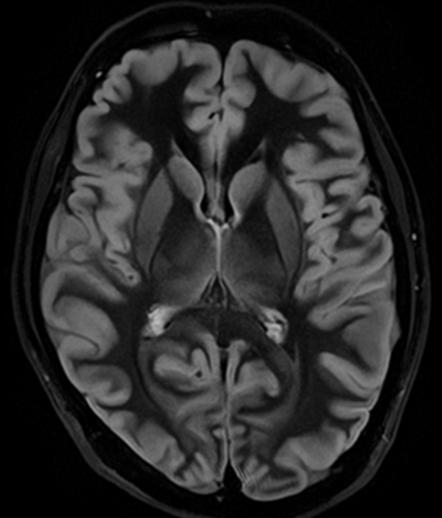

In particular DLR has an important clinical impact in anatomical regions that require a very high resolution, for example parts of the hippocampus and the claustrum.

“The DLR brings a spatial resolution that I have never seen before in neurologic imaging. I recently pointed out a brain area, for example the claustrum, that is almost invisible on standard MRI images even with very high resolution or high field devices. However, thanks

to the DLR we could highlight this kind of brain anatomy. So, indeed, there is a considerable advantage to using this technique.” Prof. Dousset said.

Prof. Tourdias worked at 7T to visualise extremely fine structures of the hippocampus while at Stanford. With DLR, he can now do this task with a 3T. “When we compared the images we realized that by pushing the 3T machine and processing with DLR that we were able to achieve a similar result to what we could achieve with 7T. I think this is the main surprise of the technology.” he said.

Atlas SPEEDER Head/Neck, T2, AiCE, Res: 0.2 x 0.2 x 2 mm, Scan time: 6:35 min.

Brain – Hippocampus

Brain Atlas SPEEDER Head/Neck, 3D FLAIR, AiCE, Res: 1 x 1 x 1.1 mm, Scan time: 4:55 min.